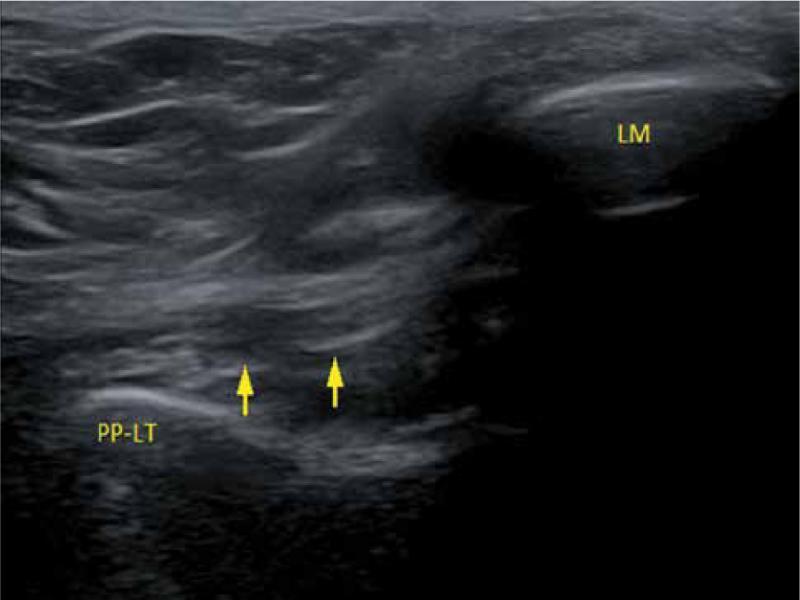

Fig. 3.

The course of PTFL on an ultrasonography image (PP-LT – lateral tubercle of the posterior process of the talus, LM – lateral malleolus, arrows – posterior talofibular ligament)

The posterior talofibular ligament connects the malleolar fossa, located on the medial surface of the lateral malleolus, with the lateral tubercle of the posterior process of the talus(1,2). In order to properly visualize PTFL, it is necessary to identify the bony structures properly, especially the lateral tubercle of the posterior process of the talus. It should be noted that ligaments, in the majority of cases, form a reinforcement for the joint capsule and as they are placed deeply, they form a tissue layer close to the bone. The structure of echogenicity and the structure typical for a ligament placed deeply and connecting the fibula with the lateral tubercle of the posterior process of the talus can be easily identified as PTFL (Fig. 2A, Fig. 3) To evaluate this ligament, we suggest to place a patient in a prone position and bend the ankle to 90 degrees in the limb undergoing examination (with feet resting on the toes – Fig. 2B), although experienced diagnosticians should not encounter problems with visualization of the ligament with a patient in the supine position with a limb bend in the knee and with the foot resting on the ground.